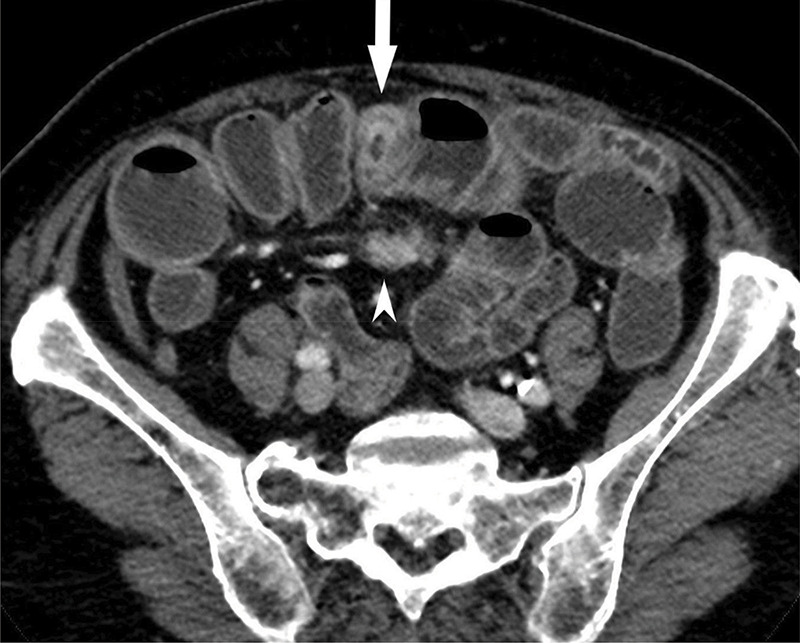

教学点:CT小肠造影/小肠灌肠术可充分评估小肠神经内分泌肿瘤及肠外异常。

Teaching point: CT enterography/enteroclysis allows adequate evaluation of neuroendocrine small bowel tumor and extra-enteric abnormalities.